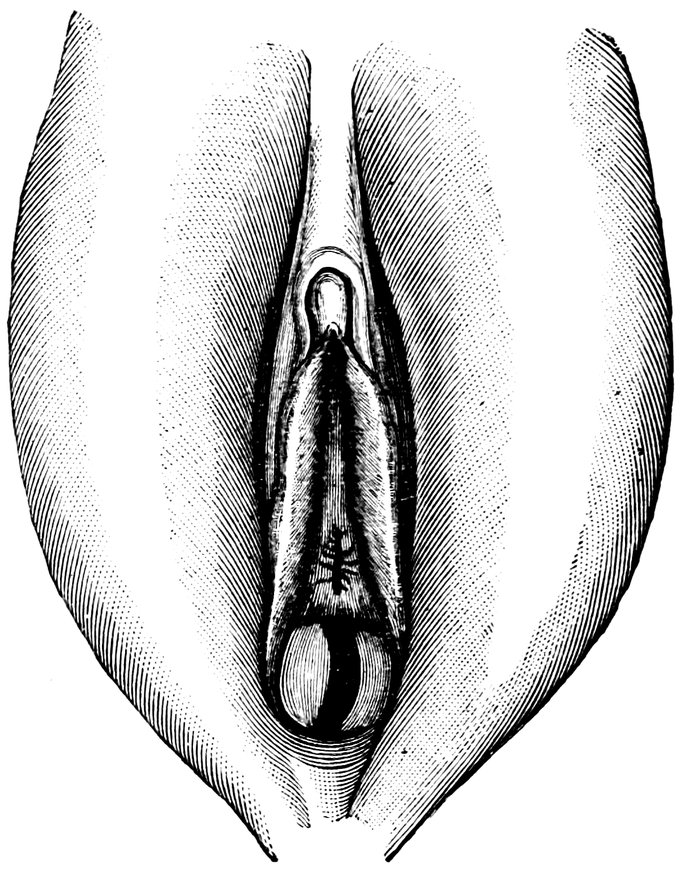

| 12. | Female external genital organs of a virgin | 54 |

| 13. | The external genital organs of a virgin | 55 |

| 48. | The female pudendum, or vulva, with the labia majora | 204 |